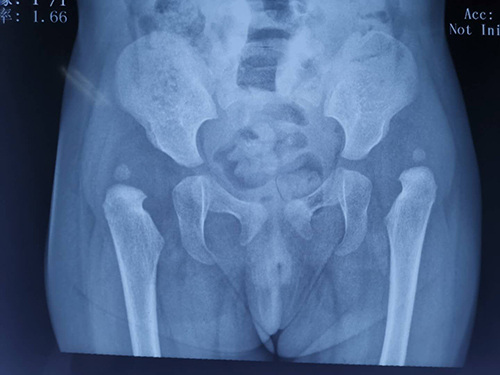

济宁市微山县的涵涵小朋友,现在已经生后15个月,同龄的小朋友基本都可以自己独立行走,但涵涵的父母发现,自己的孩子还处于蹒跚学步的状态,这种情况让他们十分着急,在亲戚及当地医生的反复建议后,慕名来山东第一医科大学附属省立医院(山东省立医院)小儿骨科,找到主任医师王恒冰就诊。王恒冰接诊后仔细询问了孩子的发育情况,并进行了仔细的体格检查、骨盆平片的检查,诊断最终明确:双侧发育性髋关节脱位。

诊断明确后,王恒冰团队术前反复讨论,仔细研究患儿的各项情况,为孩子制定了最佳的治疗方案,术后涵涵小朋友恢复良好。